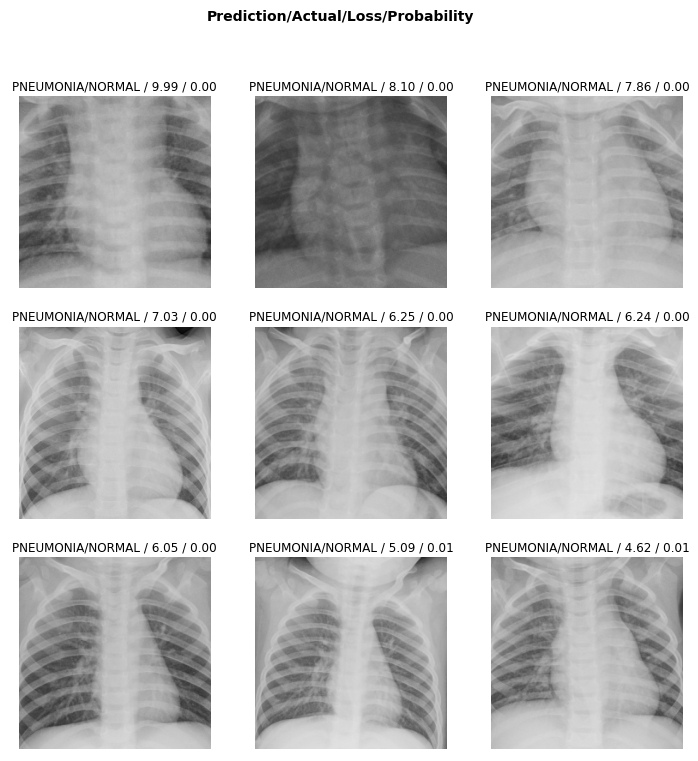

3. 가장 losses가 큰 이미지 출력해보기

interp.plot_top_losses(k=9)

의학적 지식이 없어서, 왜 잘못 분류된 건지는 잘 모르겠다. 정상인데 폐렴이라고 분류 경우가 9개 출력되었다.

여담) 예전에 코로나 관련 검사로 x-ray를 찍었는데 하얀 줄무늬가 많이 보이면 폐렴일 수 있다나 뭐라나 그러고 보니 이 이미지들이 그런 게 많아 보이기도 한다.